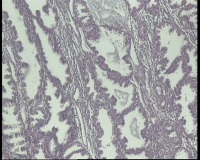

| 图片: | |

- 急!请老师看看34岁子宫内膜

| 性别 | 女 | 年龄 | 34岁 | 临床诊断 | 子宫内膜息肉? |

| 一般病史 | 末次月经:11月20日,近两个月无诱因性生活有阴道少许血性分泌物 | ||||

| 标本名称 | 宫内容物 | ||||

| 大体所见 | 膜样碎组织3.0厘米 | ||||